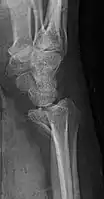

Lateral projectional radiograph of the same fracture